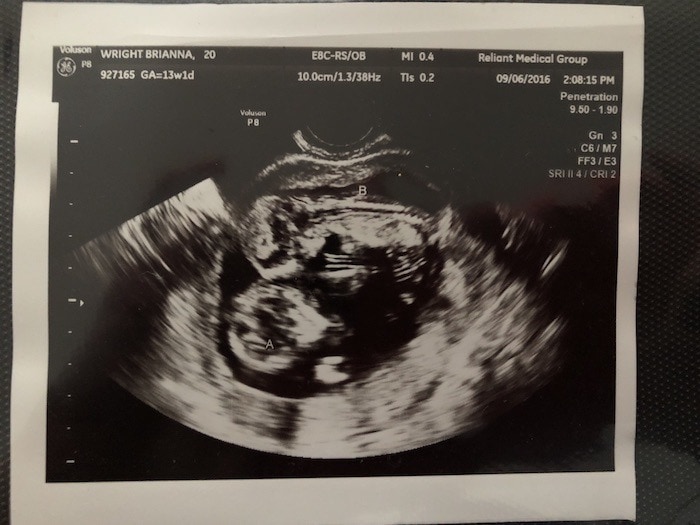

- Ultrasound Photos at 13 Weeks Pregnant With Twin

Ultrasound Photos at 13 Weeks Pregnant With Twin